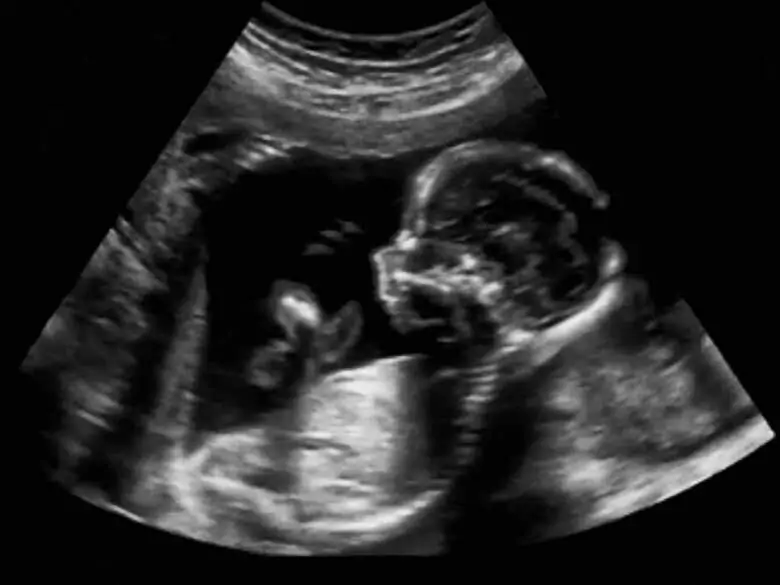

Las pruebas prenatales han desempeñado durante mucho tiempo un papel importante en ginecología y obstetricia, pero hoy en día su valor aumenta constantemente debido a que cada vez más mujeres se quedan embarazadas tardíamente. Entre las pruebas prenatales se distingue entre las invasivas y las totalmente no invasivas: ¿qué pruebas se realizan exactamente en el diagnóstico prenatal y cuándo se utiliza cada una de ellas?